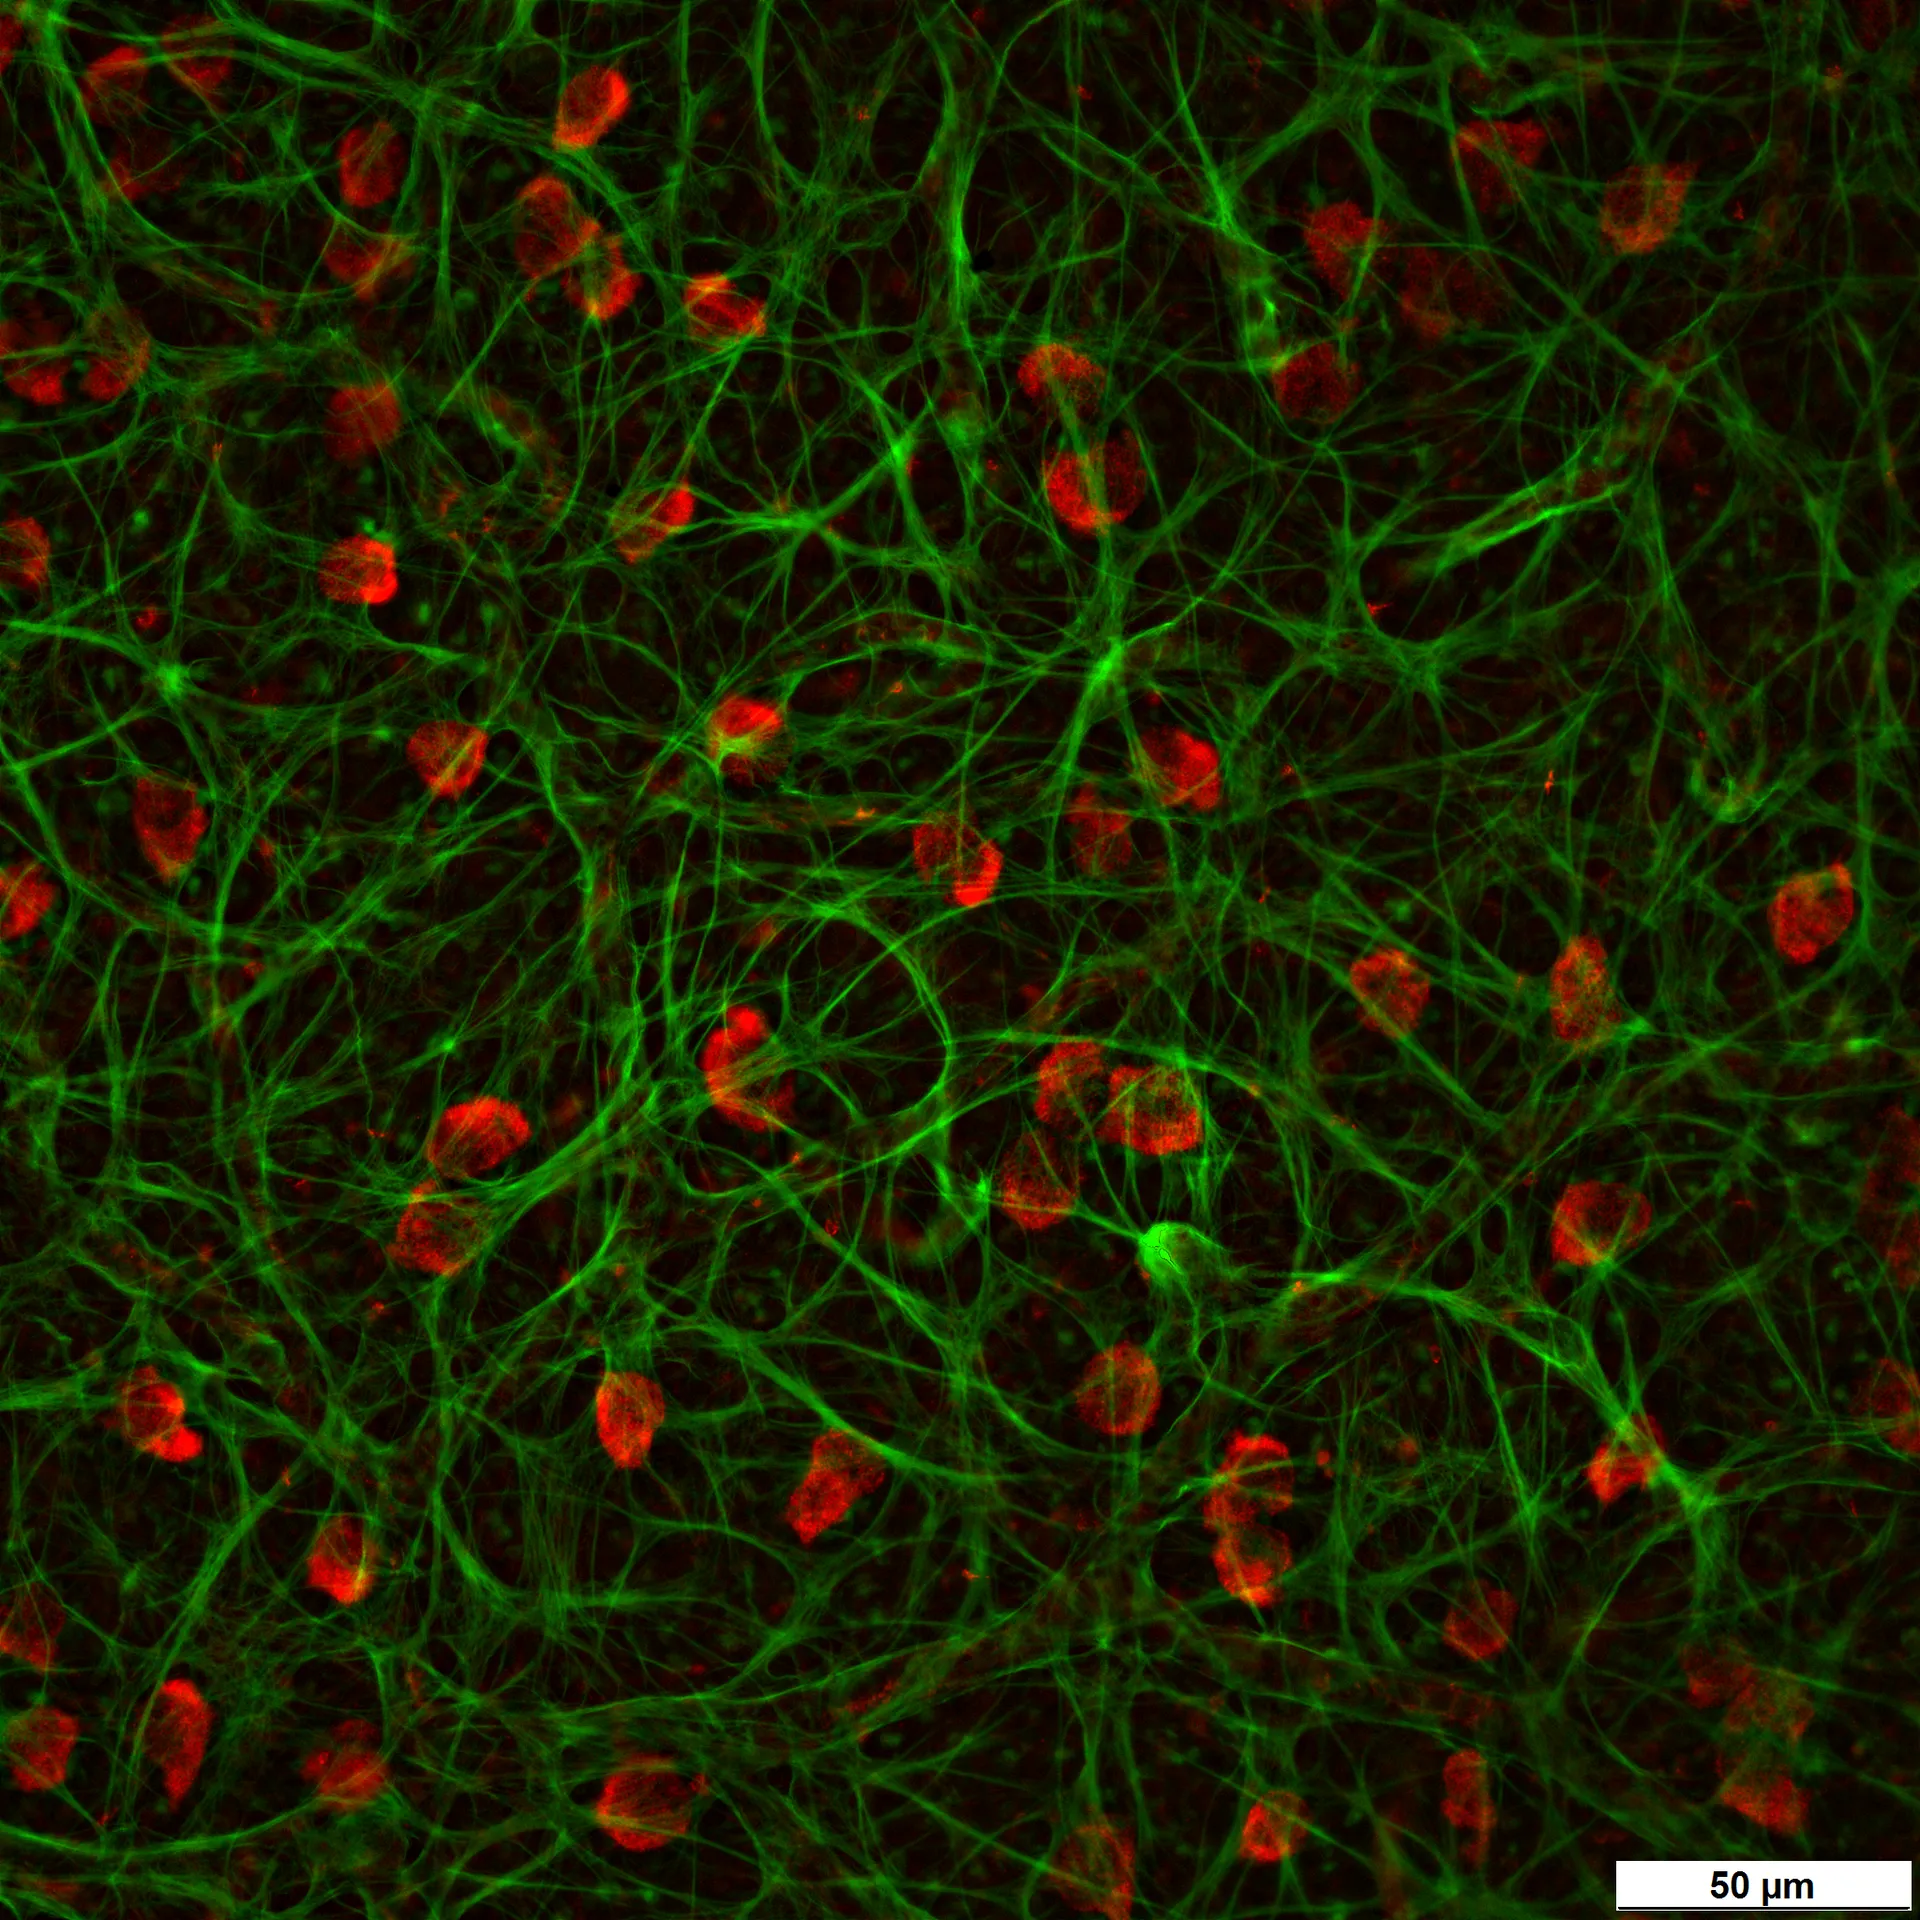

– Quantitative and unbiased estimation of RGCs from retinal flat mounts

AI-driven image analysis and stereology provide objective, reproducible RGC quantification for reliable drug efficacy assessment.